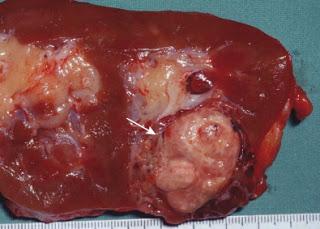

Examen microscopique "pièce fraîche" retrouvant une tumeur polaire inférieure d'aspect jaune - chamois à la coupe, caractéristique d'un carcinome rénal à cellules claires. In Annales d'Urologie Volume 41, Issue 6, December 2007, Pages 285 - 297